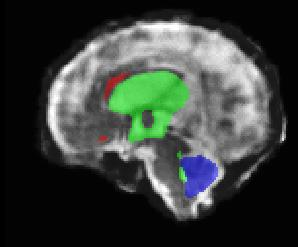

Limiting failures of machine learning systems is of paramount importance for safety-critical applications. In order to improve the robustness of machine learning systems, Distributionally Robust Optimization (DRO) has been proposed as a generalization of Empirical Risk Minimization (ERM). However, its use in deep learning has been severely restricted due to the relative inefficiency of the optimizers available for DRO in comparison to the wide-spread variants of Stochastic Gradient Descent (SGD) optimizers for ERM. We propose SGD with hardness weighted sampling, a principled and efficient optimization method for DRO in machine learning that is particularly suited in the context of deep learning. Similar to a hard example mining strategy in practice, the proposed algorithm is straightforward to implement and computationally as efficient as SGD-based optimizers used for deep learning, requiring minimal overhead computation. In contrast to typical ad hoc hard mining approaches, we prove the convergence of our DRO algorithm for over-parameterized deep learning networks with ReLU activation and a finite number of layers and parameters. Our experiments on fetal brain 3D MRI segmentation and brain tumor segmentation in MRI demonstrate the feasibility and the usefulness of our approach. Using our hardness weighted sampling for training a state-of-the-art deep learning pipeline leads to improved robustness to anatomical variabilities in automatic fetal brain 3D MRI segmentation using deep learning and to improved robustness to the image protocol variations in brain tumor segmentation. Our code is available at https://github.com/LucasFidon/HardnessWeightedSampler.